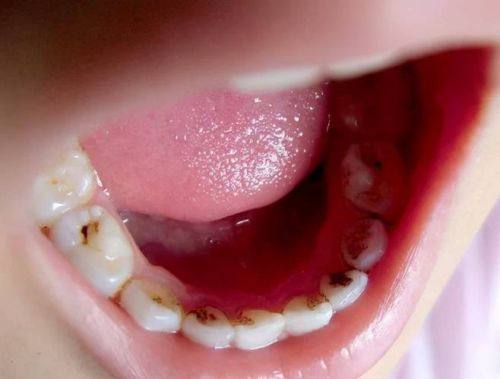

儿童齿科:接诊3-12岁儿童,开展儿童龋病治疗、早期颌面发育干预等项目,医护人员对儿童患者耐心细致,诊疗环境童趣化,降低儿童看牙的抵触情绪。

王妈妈(儿童早期干预):“我家5岁孩子有地包天,医生推荐用MRC早期干预。叶医生对孩子特别有耐心,治疗前还陪孩子玩了会儿,让孩子一点都不害怕。做了半年多,孩子的咬合情况改善了特别多,不用等换牙再遭罪。儿牙中 心的环境特别童趣,孩子现在都主动说要去看牙,真的选对了医院。”